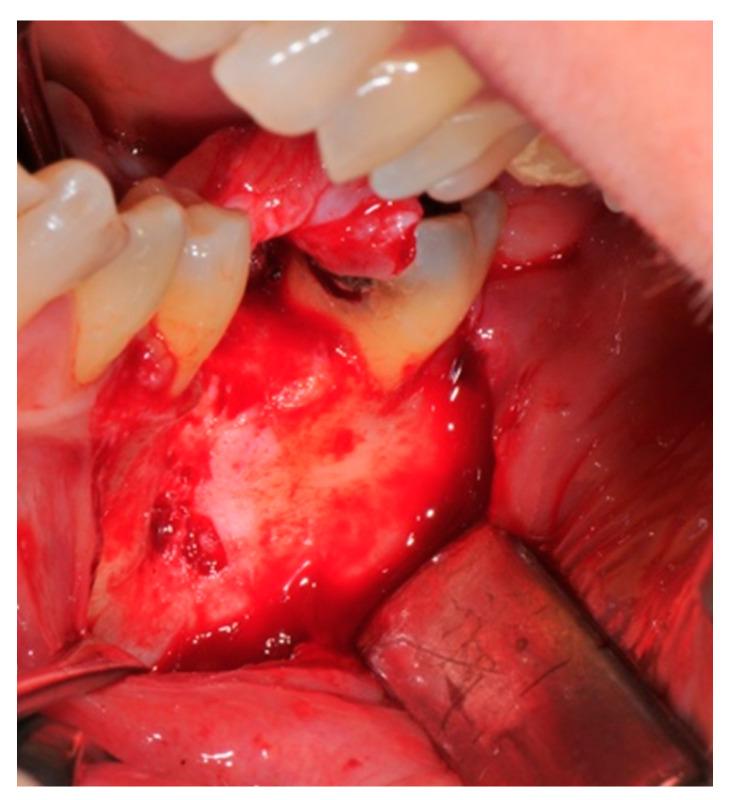

用于垂直、水平及复合骨缺损骨再生的数字化定制钛网:病例系列

Guided bone regeneration allows new bone formation in anatomical sites showing defects preventing implant rehabilitation. The present case series reported the outcomes of five patients treated with customized titanium meshes manufactured with a digital workflow for achieving bone regeneration at future implant sites. A significant gain in both width and thickness was achieved for all patients. : From a radiographic point of view (CBTC), satisfactory results were reached both in horizontal and vertical defects. An average horizontal gain of 3.6 ± 0.8 mm and a vertical gain of 5.2 ± 1.1 mm. The findings from this study suggest that customized titanium meshes represent a valid method to pursue guided bone regeneration in horizontal, vertical or combined defects. Particular attention must be paid by the surgeon in the packaging of the flap according to a correct method called the "poncho" technique in order to reduce the most frequent complication that is the exposure of the mesh even if a partial exposure of one mesh does not compromise the final outcome of both the reconstruction and the healing of the implants.

引导性骨再生可使解剖部位形成新骨,这些部位存在妨碍种植体修复的缺损。本病例系列报告了5例患者的治疗结果,这些患者采用数字化工作流程制造的定制钛网,以实现未来种植部位的骨再生。所有患者在宽度和厚度上均有显著增加。从影像学角度(CBTC)来看,水平和垂直缺损均取得了满意的结果。平均水平增加3.6±0.8毫米,垂直增加5.2±1.1毫米。本研究结果表明,定制钛网是在水平、垂直或联合缺损中进行引导性骨再生的有效方法。外科医生必须特别注意根据一种称为“雨披”技术的正确方法来包扎皮瓣,以减少最常见的并发症,即钛网暴露,即使一个钛网部分暴露也不会影响重建和种植体愈合的最终结果。